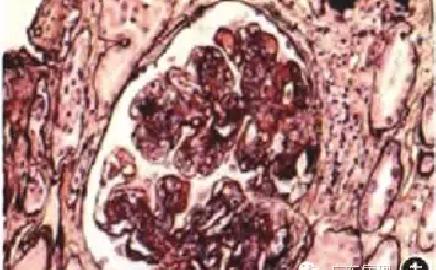

肾活检病理诊断的特点

无症状蛋白尿及血尿